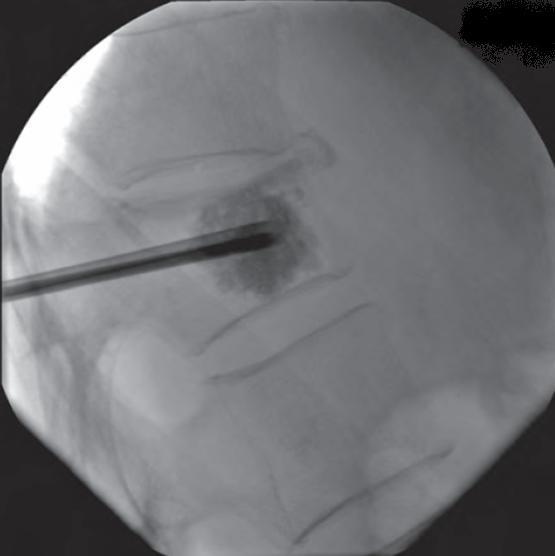

Imagem de raio-x intra-operatório com agulha locada próximo ao centro do corpo vertebral.